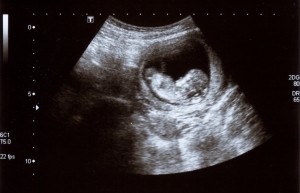

Dzieki dziewczynki leze od 3 godzin ale wiem ze będzie ok i to jest najważniejsze zdrowie maluszka

Leż, leż. Wiem, że to ciężko, ale dasz radę!Dzieki dziewczynki leze od 3 godzin ale wiem ze będzie ok i to jest najważniejsze zdrowie maluszka ������

No niestety, wszystko się rozciąga. Ja nie mam wyrostka, więc może też to być przyczyną, że bardziej boli, bo jednak blizna jest również w środku.Malutka mnie tez ciagle cos kłuje czasem z prawej a czasem tak jakby od środka. Jajnik tez czasami i więzadla jak czasem zaciągną ale przecież wszystko tam sie rozciàga.